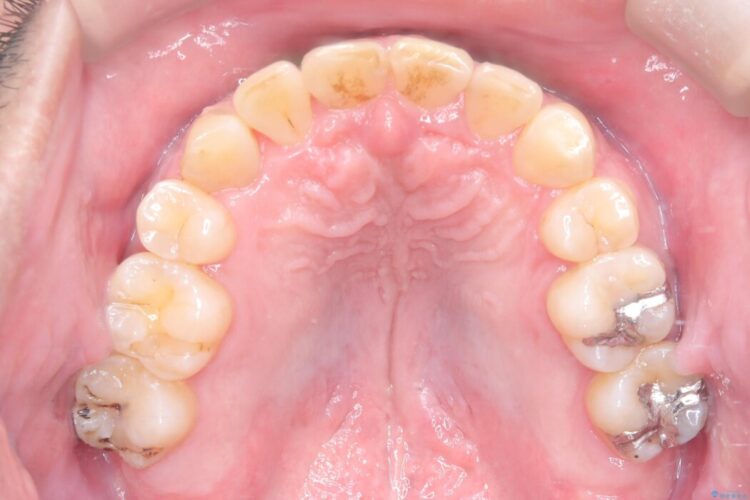

診査の結果、上下左右4番の歯を抜歯し、審美装置にて反対咬合と叢生を改善していくこととしました。

骨格性Ⅲ級を示しましたが、構成咬合位がとれたことから反対咬合と叢生改善のため、上下左右第一小臼歯を抜歯しワイヤー矯正を行いました。途中、バイトアップを行っています。